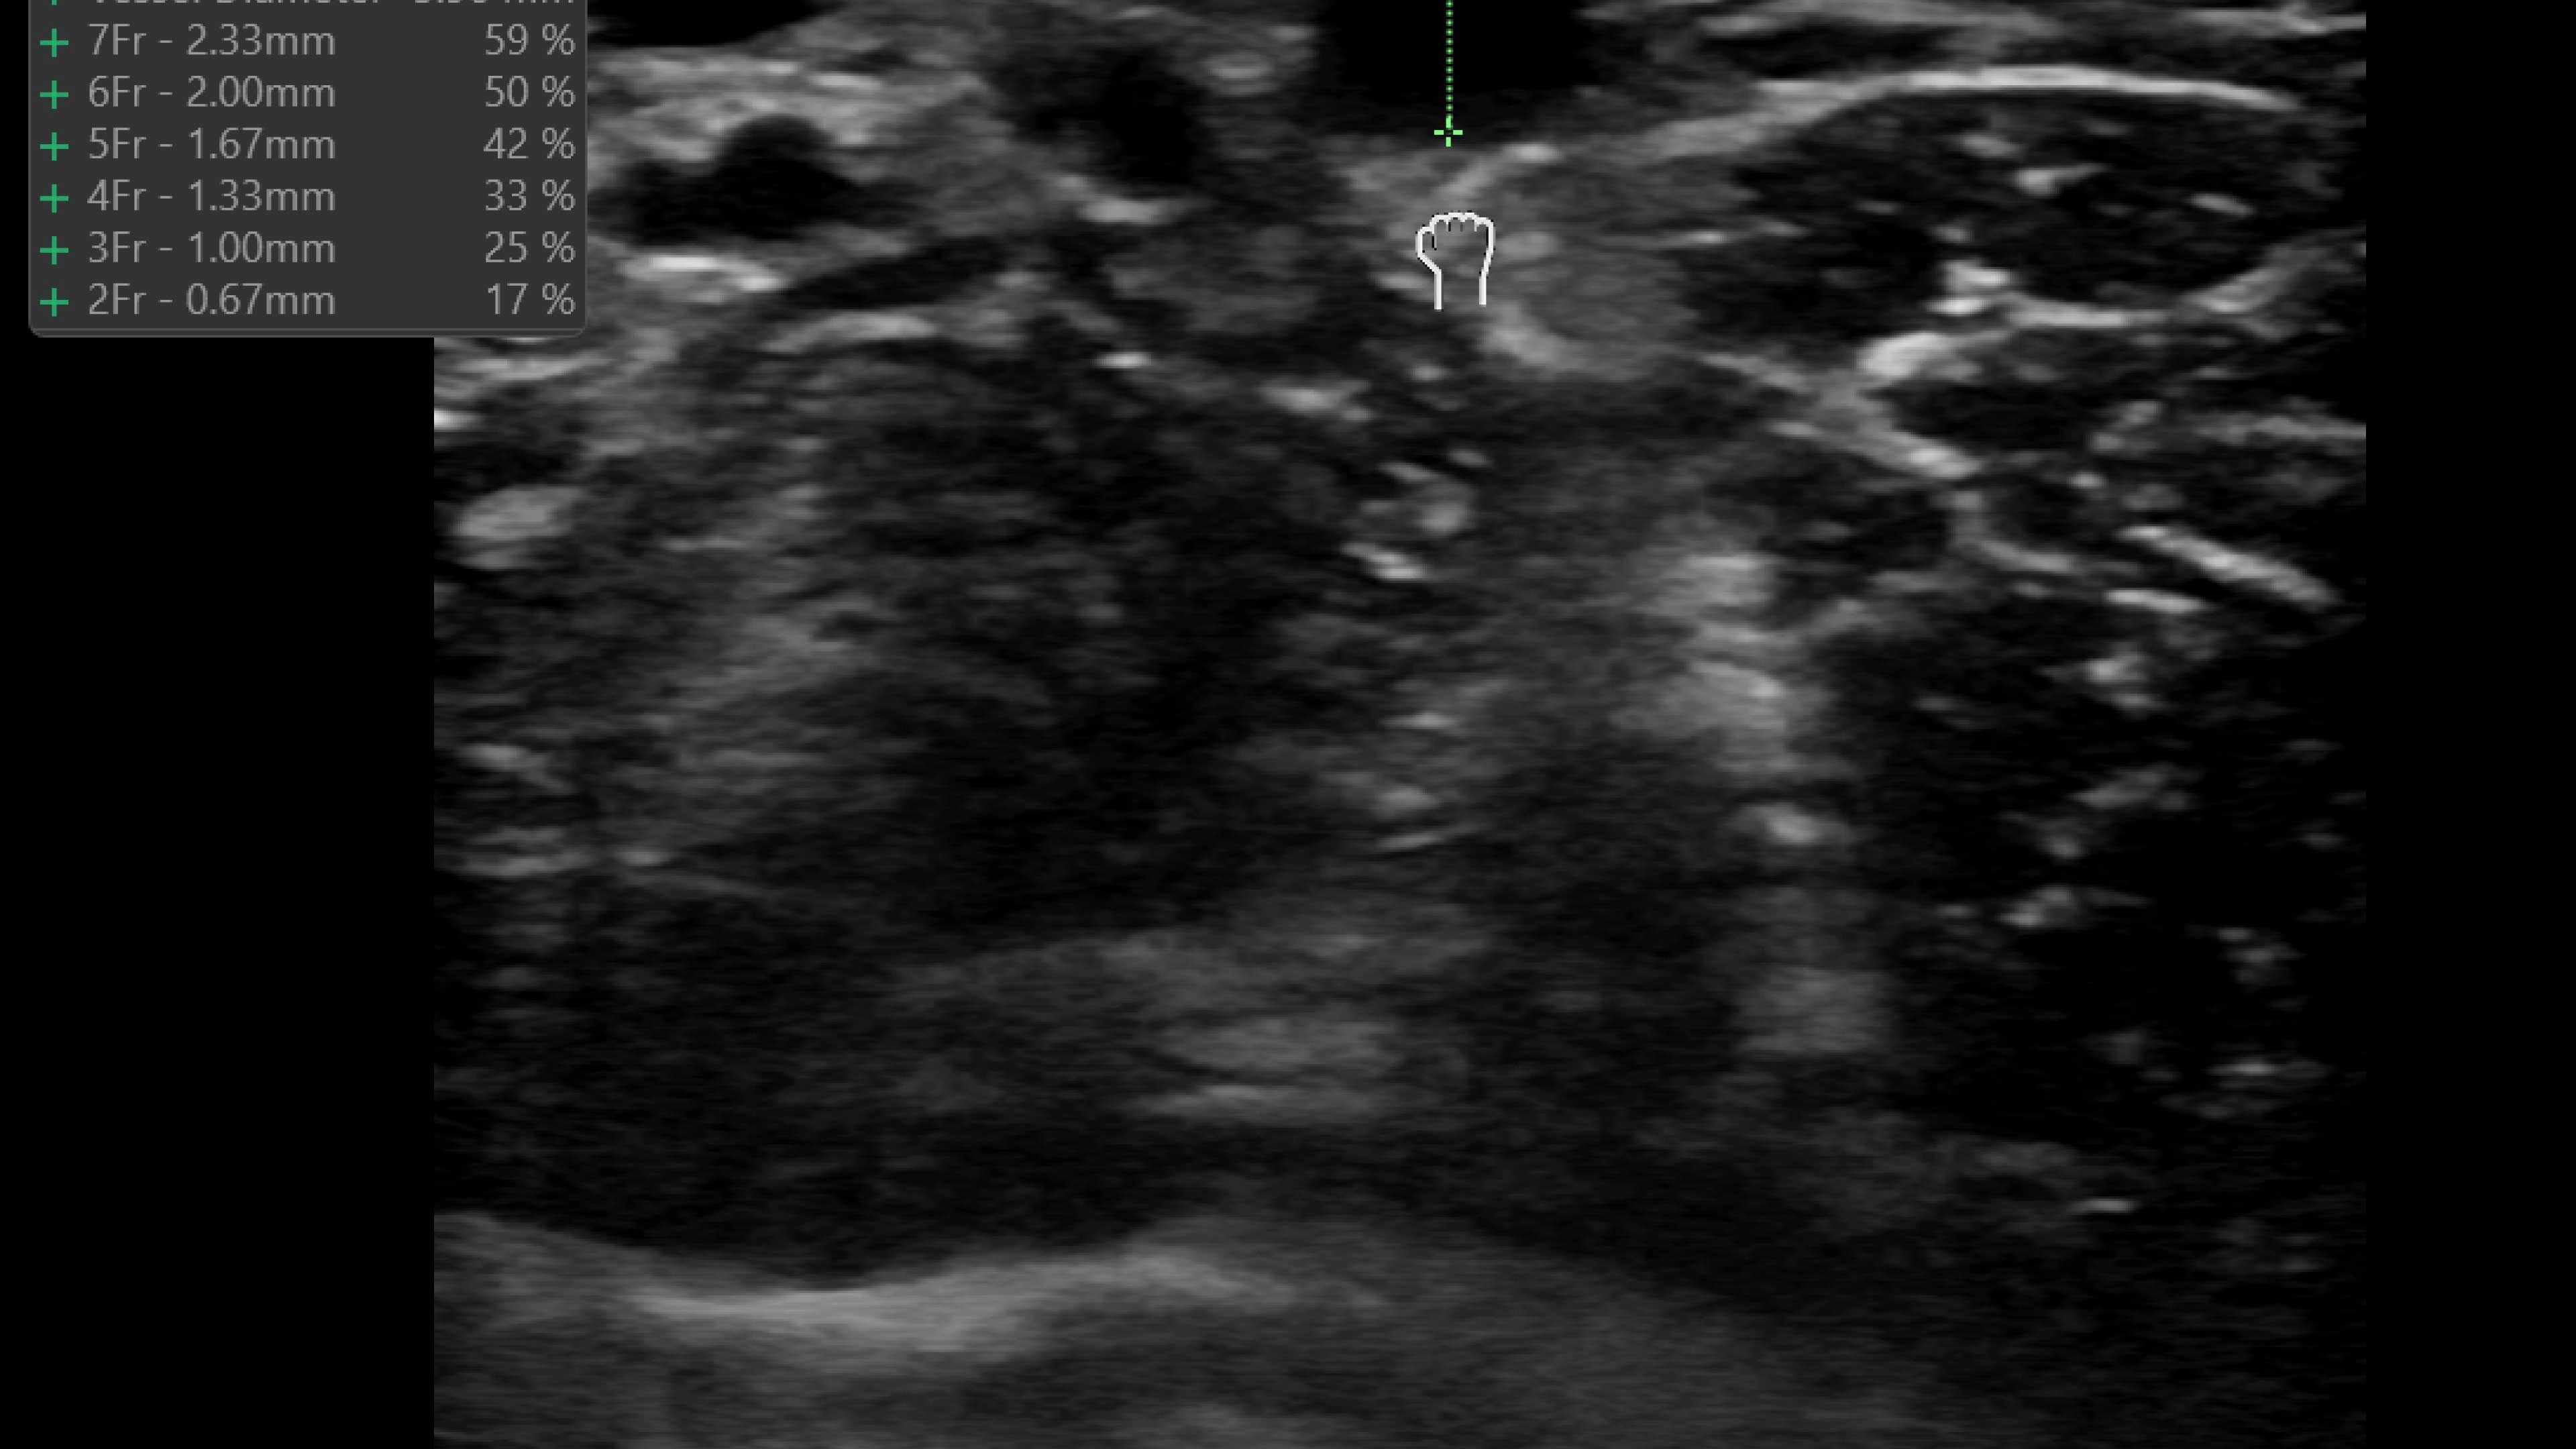

Vascular access

Helps you to assess vascular diseases, from cardiovascular conditions and peripheral vascular disease to pulmonary vascular disease.